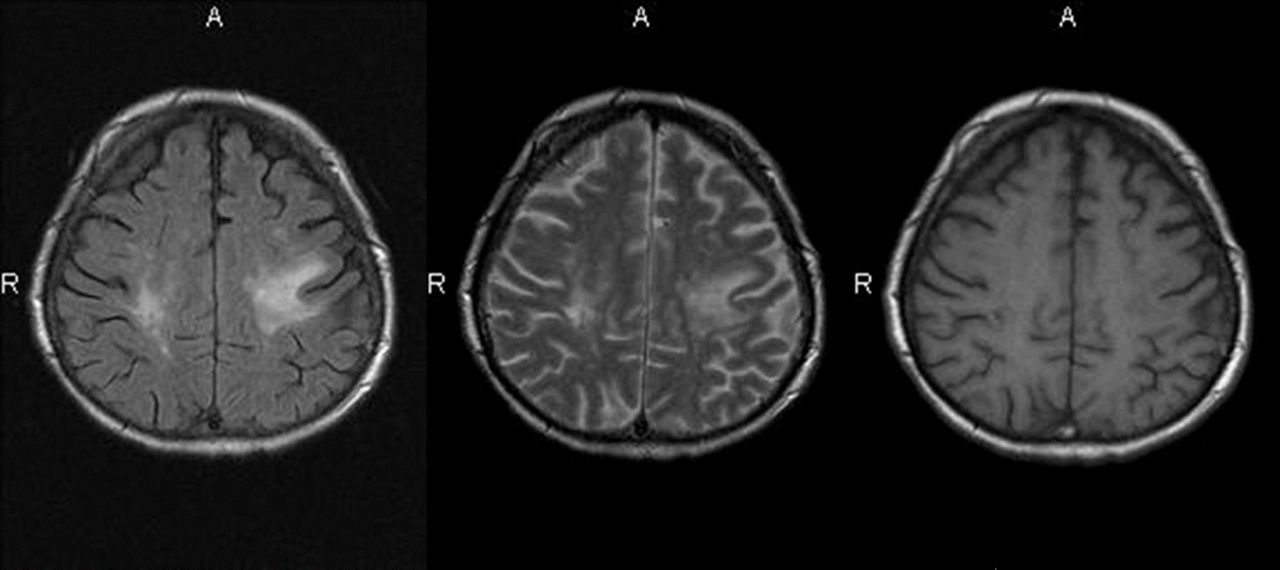

Abb. 1: Bei Vorstellung großflächige Läsion

Abb. 2: Leichte Besserung

Abb. 3: Nach 2 Monaten: Ausweitung der flächigen Läsionen mit zystischen Anteilen

Abb. 4: Nach 2 Monaten

Abb.6: 4 Monate nach Vorstellung: Zunahme der flächigen Marklage-Läsionen und der zystischen Defekte